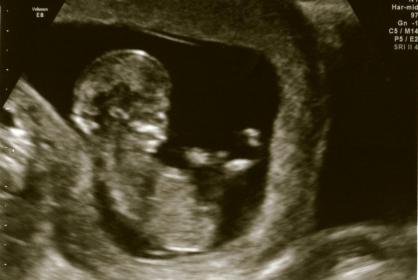

Any guesses? Thank you in advance!!!

No nub.

I don't see a nub either

Leaning boy

I can't see a nub in the picture. Doesn't necessarily mean girl, just not a great shot...

no nub but a boyish skull